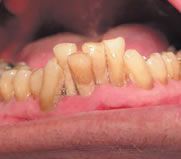

Eine bakteriell bedingte Entzündung, die sich in einer weitgehend irreversiblen Zerstörung des Parodontiums zeigt, wird als Parodontitis bezeichnet.

Eine initiale Diagnostik kann eine Fotodokumentation, die Erstellung diverser Indizes (z. B. Plaqueindex, API/ SBI) und Röntgenaufnahmen beinhalten. Bei den Röntgenaufnahmen wird eine Panoramaaufnahme (OPG) angefertigt. Von nicht vital reagierenden und wurzelgefüllten sowie nicht im OPG ausreichend erkennbaren Zähnen werden Zahnfilme erstellt.

Die Röntgendiagnostik gibt Auskunft über Zustand, Form und Beschaffenheit von Zahnhartsubstanz, Alveolenknochen, Desmodontalspalt und Restaurationen.